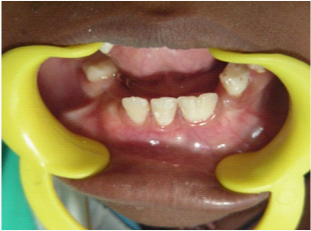

A 10 year old boy reported to the Department of Pedodontics and Preventive Dentistry, Narayana Dental College, Nellore, Andhra Pradesh for routine dental check-up, presented with a large tooth in the lower left front region of the jaw (Figure 1). The boy was not concerned about the aesthetic appearance. The medical and family histories were not significant. Extraoral examination did not show any alterations. Intraoral examination revealed an early mixed dentition period with the presence of one large incisor that was abnormally wide on the left side of the lower arch (Figure 2 and 3). The child had 20 teeth and normal eruption pattern and occlusal status was evident. The double tooth presented a groove upto the cervical third of the crown and hypoplasia on the labial surface (Figure 4). Periapical radiograph displayed the connated incisor with a single root and single pulp canal (Figure 5). The orthopantomograph revealed the presence of double tooth along with the absence of lower left lateral incisor (Figure 6).

Figure 2The mandibular arch showing the connated tooth.

Figure 3 Close up view of connated teeth showing a groove that extends upto the cervical third of the crown.